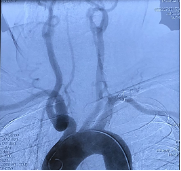

2020.07.03燕达医院

4.入路血管损伤

治疗过程:患者多参数监护仪监测下,全麻满意后,常规消毒铺巾,采用改良Seldinger技术穿刺右侧股动脉成功,置入8F动脉鞘。经右侧股动脉鞘,黑泥鳅带领长鞘(Penumbra Neuro MAX6F )到达右侧颈内动脉岩段,撤下泥鳅导丝,微导丝(Synchro 0.014 in*200 cm)带领支架微导管(Prowler Select Plus)达右大脑中动脉M1段,撤出微导丝,再次用微导丝(Synchro 0.014 in*200 cm)带领微导管(Echelon10eV3)超选到达眼动脉段动脉瘤内,退出微导丝。经Echelon10微导管送入(Codman COMPLEX XTRASOFT 3 mm×8 cm)弹簧圈一枚成篮并未解脱,后经支架微导管释放支架一枚(Codman ENTERPRISE 4.5 mm*22 mm)支架打开良好,覆盖瘤颈,撤出支架微导管后解脱首枚弹簧圈,复查造影,弹簧圈位置形态良好,解脱后继续送入(Codman COMPLEXXTRASOFT 2.5 mm×3.5 cm; EV3 3D 1 mm×2 cm;EV3 3D 1.5 mm×4 cm)3枚弹簧圈,期间间断造影确保眼动脉段血流通畅,栓塞后复查脑血管造影,动脉瘤区未见显影,未见造影剂渗漏。手术结束。缝合器缝合右股动脉穿刺点,加压包扎。术后患者麻醉清醒,拔除气管插管,呼唤应答,对答切题,言语清楚,四肢肌力肌张力正常。